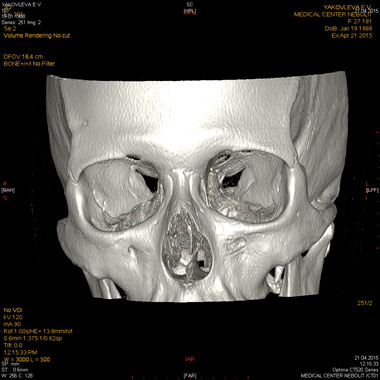

МСКТ придаточных пазух носа, лицевого черепа, орбит

Показания:

- подозрение на опухоль, кисту

- воспалительные заболевания при отсутствии эффекта от бактериальной терапии

- травма

- аномалии развития

Подготовка: не требуется.

Предварительное рекомендуемое обследование: заключение оториноларинголога